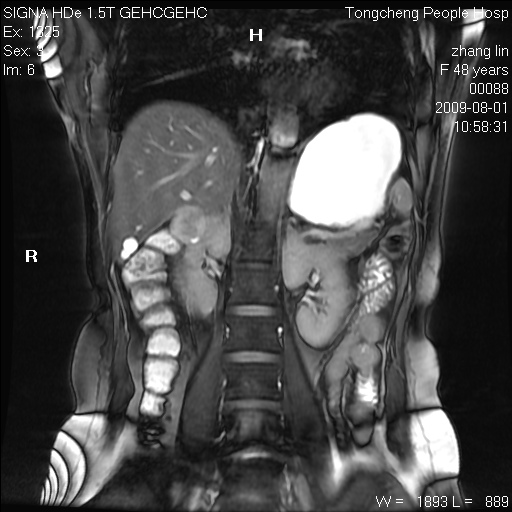

女,48岁。健康体检,彩超发现右肾占位性病变。平素健康。

临床诊断:右肾占位性病变,性质待定(囊肿?肿瘤?)。

上中腹部mr平扫+增强扫描,图像如下:

右肾上极见一类圆形病灶,t1wi呈等信号t2wi呈等高混杂信号,三期增强无强化,边界清---考虑囊肿出血。